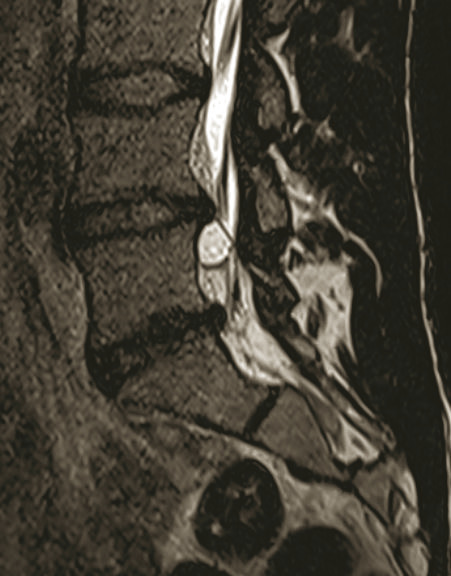

L’IRM du rachis lombaire obtenue une semaine plus tard retrouve une formation kystique développée en postéro-latéral droit du corps vertébral de L5 venant comprimer la racine L5 droite et affleurant la racine S1 droite à son émergence, évocatrice d’un kyste arthrosynovial extramédullaire et extradural (photos).